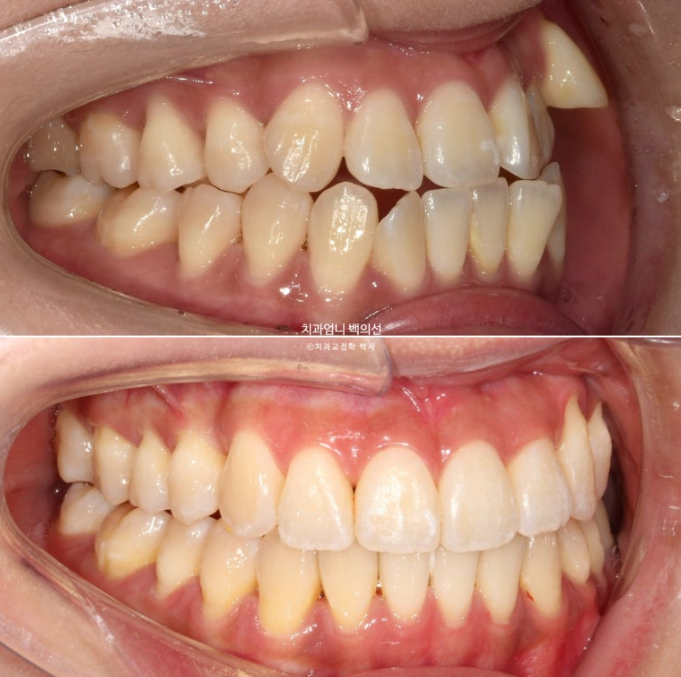

23.09~25.03

앞니가 거꾸로 물리던 부분도 정상교합을 찾았습니다

얼굴과 맞아진 치아 중심선과 깔끔한 스마일라인

미소가 한결 예뻐지고 자연스러워졌습니다.

아래 앞니가 사랑니 공간을 이용하여 뒤로 2mm 후방이동 했습니다.

앞니 반대교합과 절단교합이 해소가 되며 아랫입술 역시 뒤로 2mm 들어갔습니다.

위 앞니는 목표대로 앞으로 나오지 않게 치료가 잘 되어 윗입술은 변화가 없습니다.